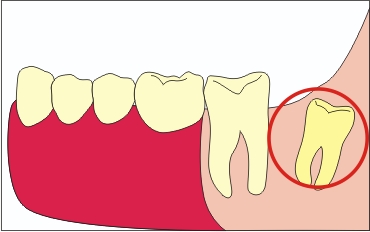

Impaktált nyolc (nem vágjuk)

Figyelhető meg, amikor helyet a fogsor. Ez a legbonyolultabb eset.

Retenirovannyh nyolc vízszintes

Az utolsó két ponyva észlelt csak útján X-ray. Ideális esetben egy ilyen fogat el kell távolítani a lehető leghamarabb, amíg már nem volt komplikáció.